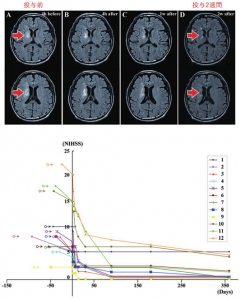

脳梗塞患者12名に対して自己骨髄性間葉系幹細胞の静脈投与を実施した結果、脳梗塞巣体積の減少がみられ、12人中7人でNIHSSスコア(脳卒中重症度スコア:高値は悪い)が改善。

幹細胞投与後も、出血、肺塞栓症、腫瘍化等の重篤な合併症は無く、有効性を確認。

また、脳梗塞発症から130日以後に幹細胞を投与したところ、脳梗塞巣体積が縮小し、NIHSSも8→0点へ改善しました。これにより幹細胞投与は慢性期であっても効果があると考えられ、また、自己骨髄性間葉系幹細胞の静脈投与により、脊髄損傷、脳梗塞、再発の予防、動脈硬化の改善、認知症・心不全・腎不全・肝不全・アンチエイジング等の効果が続々と明らかになっています。

Honmou et al., Brain 134:1790-1807, 2011